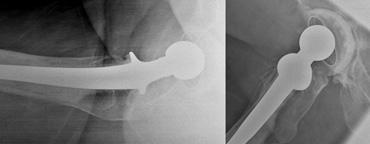

Different anteversion of the acetabular cup in the same patient due to different rotation on a cross table view (left) compared to a lateral view (right).

Độ nghiêng trước của ổ cối nhân tạo nên nằm trong khoảng 5-25°.

Không thể đo chính xác góc này trên phim chụp X-quang tư thế ngang bàn hoặc tư thế nghiêng thực sự, vì mức độ góc nghiêng biểu kiến trên phim X-quang bị ảnh hưởng bởi sự xoay của khung chậu hoặc đùi (hình).

Đo bằng CT chính xác hơn, nhưng vẫn phải bù trừ cho góc nghiêng của khung chậu.

LEFT: Femoral head with large collar. Dislocation due to increased lateral inclination of acetabular cupRIGHT: Different patient at risk for dislocation. High and lateral position of a steep acetabular cup. Notice polyethylene wear due to increased forces on the superolateral side of the cup.

The following conditions predispose to dislocation:

– Tăng góc nghiêng ngoài của cốc acetabular.

– Giảm hoặc tăng góc anteversion của cốc.

– Vị trí quá ngoài của cốc acetabular.

– Tăng hoặc giảm góc anteversion của thân xương đùi.

Do lực tác động tăng lên ở bờ trên ngoài của ổ cối, việc tăng độ nghiêng ngoài của cấu phần ổ cối cũng có thể làm tăng nguy cơ mòn polyethylene của lớp lót ổ cối (xem hình).

Vị trí ưu tiên của thành phần xương đùi là với thân khớp nằm ở trung tâm ống tủy xương đùi.

Tâm xoay của chỏm xương đùi phải nằm ở mức đỉnh của mấu chuyển lớn.

Vị trí varus của thân khớp xương đùi là yếu tố thuận lợi dẫn đến lỏng khớp và gãy xương.